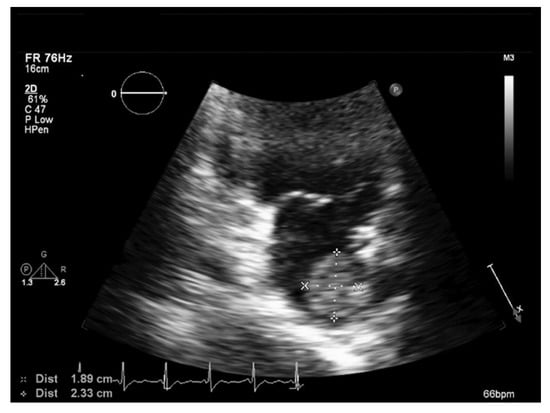

2. Case Presentation